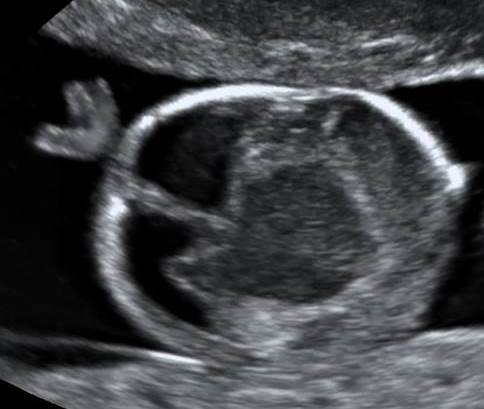

Срок 22 недели.

Какая патология перед нами? Затылочный рог справа 13.2 мм